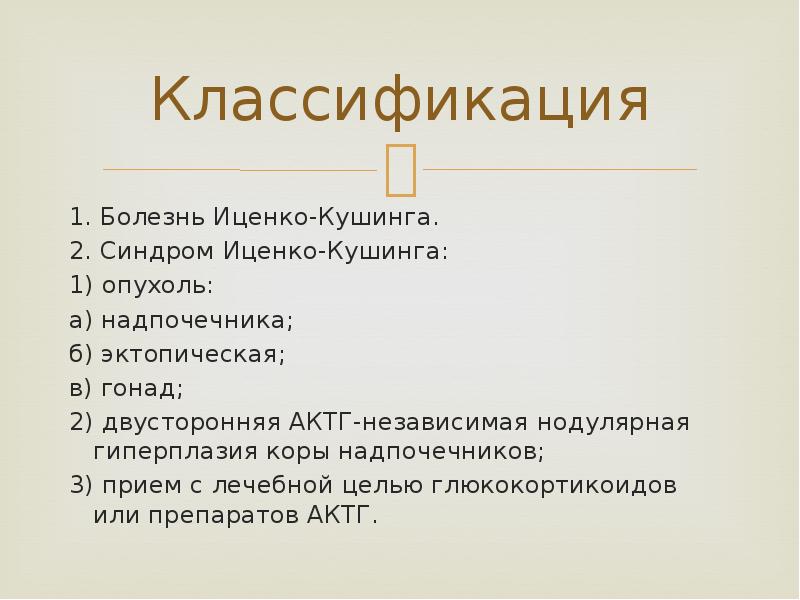

Классификация

1. Болезнь Иценко-Кушинга.

2. Синдром Иценко-Кушинга:

1) опухоль:

а) надпочечника;

б) эктопическая;

в) гонад;

2) двусторонняя АКТГ-независимая нодулярная гиперплазия коры надпочечников;

3) прием с лечебной целью глюкокортикоидов или препаратов АКТГ.